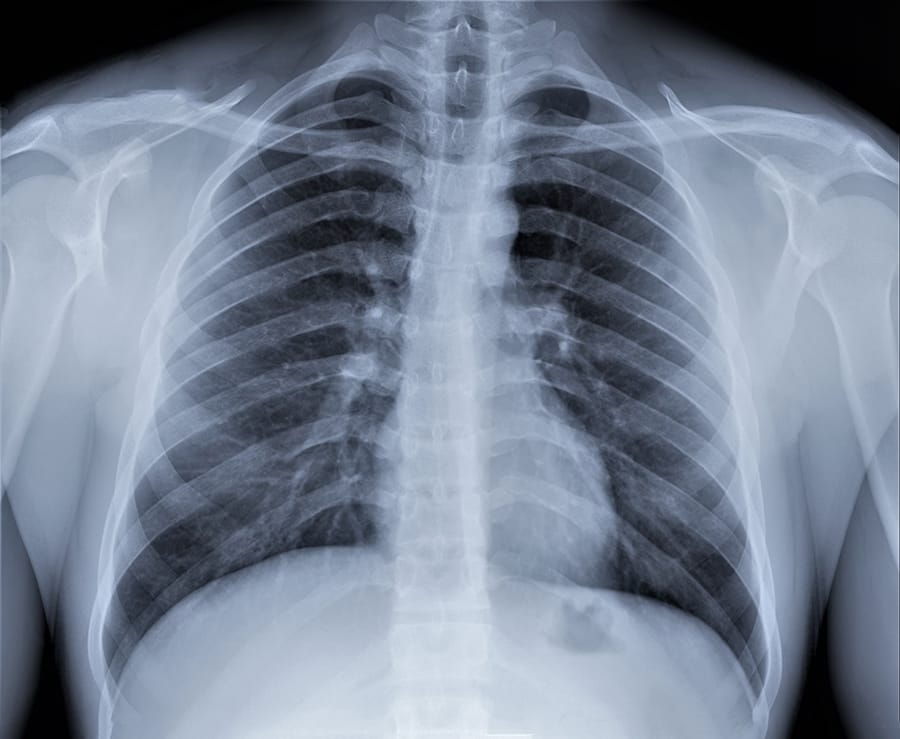

Rontgen paru-paru diperlukan untuk mengevaluasi perubahan yang terjadi pada penderita Covid-19.

Covid-19 adalah penyakit yang menyerang saluran pernapasan manusia. Virus dapat masuk ke tubuh melalui mata, hidung, dan mulut. Ketika virus ini masuk ke dalam tubuh, maka virus akan berkembang biak dan menyebabkan infeksi pada organ paru-paru. Kondisi ini dapat dilihat dari hasil rontgen yang menunjukkan adanya area dengan kabut putih di paru-parunya. Infeksi virus Covid-19 dimulai dari tenggorokan sampai alveolus. Kondisi tersebut akan menyebabkan paru-paru meradang dan membengkak hingga akhirnya terisi cairan.

Pada tahap ini, hasil rontgen dada diperlukan untuk mengevaluasi perubahan yang terjadi ketika seseorang terpapar virus Covid-19. Hasil rontgen digunakan dokter untuk mendiagnosis apakah orang tersebut terinfeksi virus Covid-19 atau tidak. Selain itu, juga digunakan untuk memantau bagaimana perkembangan infeksi yang disebabkan oleh virus Covid-19.

Jadi, dalam kasus Covid-19, hasil rontgen menjadi bagian penting untuk mengetahui kondisi paru-paru Anda. Virus Covid-19 yang menginfeksi seseorang dapat berupa infeksi ringan hingga berat. Untuk mereka yang masih baru terinfeksi, perubahan tidak akan terlihat dari hasil rontgen dada. Sebab, virus belum menginfeksi secara luas sehingga belum terjadi perubahan. Selanjutnya, ketika tahap infeksi mulai mengarah ke kondisi yang semakin berat. Maka hasil rontgen akan menunjukkan perbedaan. Penjelasan di bawah ini dapat membantu Anda mengetahui hasil rontgen seseorang yang terkonfirmasi positif dari ringan hingga berat.

Pasien yang berada pada tahap infeksi ringan akan menunjukkan gejala gatal di tenggorokan dan mengalami batuk kering. Selain itu, pada beberapa kasus, peradangan di paru-paru dapat terjadi dan sebagian orang sehingga mengalami kesulitan saat bernapas. Dalam kondisi ini, saat dilakukan rontgen paru maka hasil akan menampakkan adanya gambaran buram pada salah satu atau kedua paru-paru. Hal itu menunjukkan bahwa terdapat infeksi yang menyerang paru-paru.

Tampilan hasil ronten paru-paru diagnosis pneumonia coronavirus.

Hasil rontgen yang terpapar Covid-19 pada tahap moderate

Pada tahap moderate, paru-paru mulai mengalami kerusakan dan mulai terisi oleh cairan. Akibatnya, pada tahap ini pasien mengalami sesak napas atau bernapas lebih cepat. Saat pemeriksaan rontgen paru-paru dilakukan, maka hasil rontgen akan menunjukkan secara jelas kalau di paru-paru Anda mulai terdapat bercak-bercak atau area putih.

Hasil rontgen yang terpapar Covid-19 pada tahap severe

Pada pasien yang telah memasuki tahap severe, paru-paru telah menunjukkan kerusakan parah, sehingga akan menyulitkan kinerja paru-paru saat bernapas. Selain itu, secara klinis, pasien dapat mengalami sindrom gangguan pernapasan akut (ARDS). Pada kondisi ini, kebanyakan orang akan membutuhkan alat bantu untuk bernapas seperti ventilator. Saat dilakukan pemeriksaan rontgen dada, maka hasilnya akan menunjukkan bahwa paru-paru Anda sudah terlihat penuh dengan kabut atau warna putih di keduanya.

Berbeda dengan mereka yang tidak merokok dan memiliki pola hidup sehat, risiko terkena infeksi parah akan lebih rendah. Hal ini karena kondisi paru-paru mereka yang masih tergolong sehat. Ketika dilakukan rontgen dada, hasil rontgen yang terlihat akan lebih banyak menunjukkan area berwarna hitam ketimbang putih.

Selain itu, berdasarkan penelitian di jurnal Radiological Society of North America, tidak semua orang yang terinfeksi positif Covid-19 mengalami perubahan pada paru-parunya saat dilakukan rontgen dada. Sekitar 70% orang menunjukkan adanya perubahan seperti ada bercak putih di paru-paru dan sekitar 30% tidak mengalami perubahan apapun saat terinfeksi Covid-19. Kesimpulannya, tidak semua orang yang positif terinfeksi Covid-19 akan menunjukkan perubahan pada paru-parunya saat dilakukan rontgen dada.